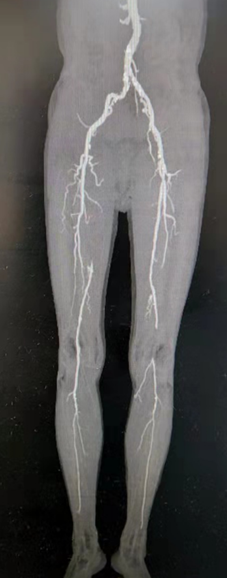

下肢CTA:1、腹主动脉及双下肢动脉多发管壁粥样硬化改变,伴右侧股浅动脉近中段、左侧腘动脉近段、双侧胫前动脉中远段、右侧胫后动脉中远段及左侧胫后动脉多发管腔闭塞,双侧髂内动脉及双侧胫前动脉近段多发管腔重度狭窄,多条动脉多发管腔轻中度狭窄,腹主动脉远段多发斑块溃疡。2、双侧足底动脉显影不佳

图片